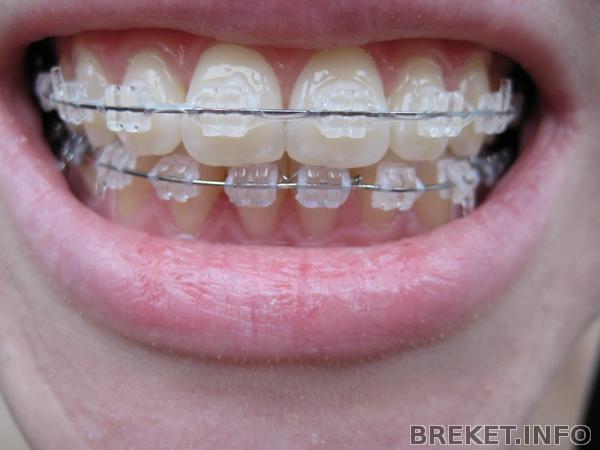

Была на приеме. Поменяли лигатурки, поставила прозрачные вместо розовых) Зубки выглядят по-другому сразу.

На ВЧ одели чейн почти на всю челюсть, потому что с одной стороны тоже небольшой промежуточек есть.